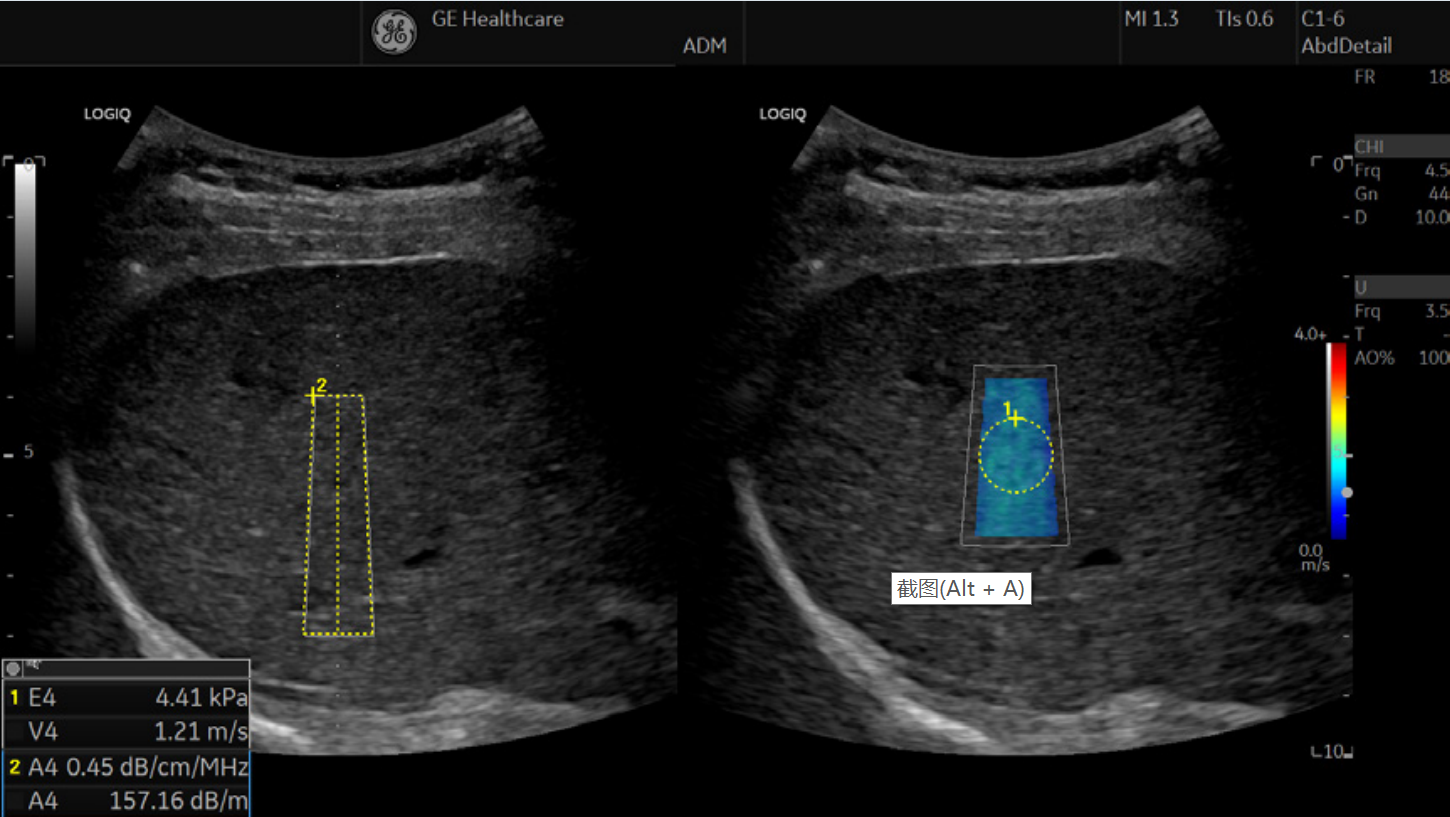

同步定征:

复合剪切波弹性图与声衰减图同步成像

同屏同时评估不同的成像参数测值